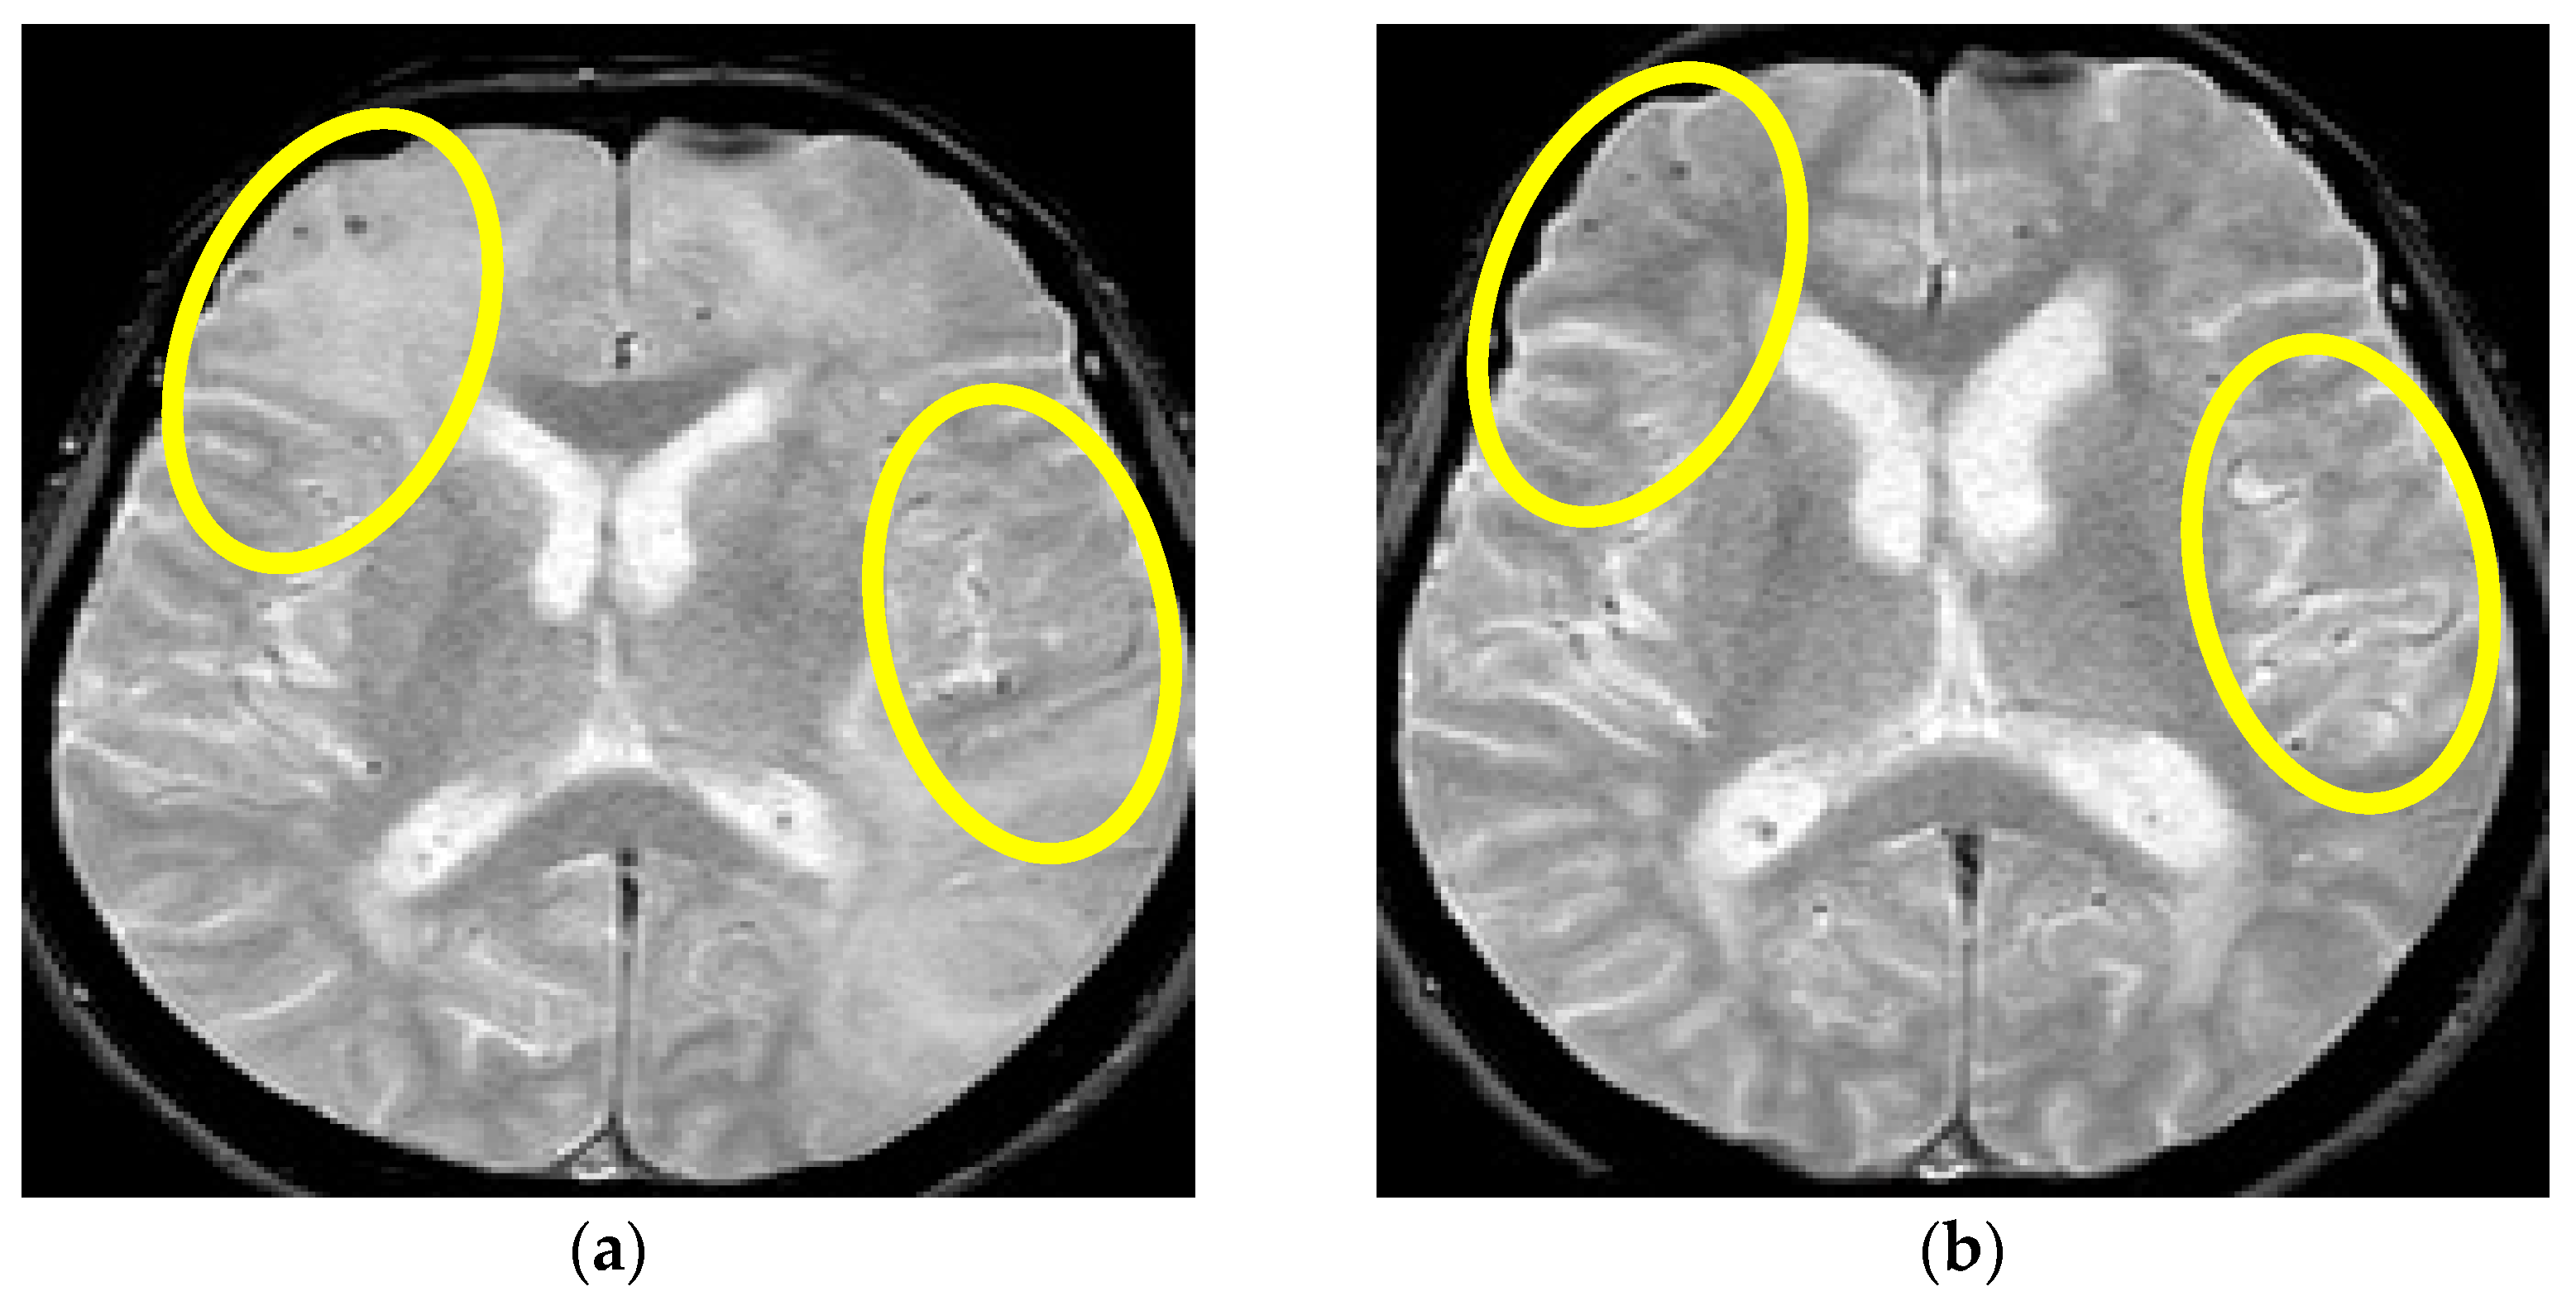

Figure 5.

MR axial T2*W sequence (a,b) showing multilocal punctiform signal hypointensities located diffusely in the subcortex and periventricular posterior region (lobar distribution). Yellow circles in (a) are showing multiple multifocal punctiform hypointensities dominantly right frontotemporally and occipitally, and in (b) bitemporal multifocal hypointensities (Patient No. 3).

Because of high clinical suspicion of probable CAA-rI, the treatment with pulse methylprednisolone therapy (1 g/daily) for 5 days was initiated, followed by oral prednisone (1 mg/kg) and azathioprine introduction (50 mg/day, as a corticosteroid sparing agent). The patient’s condition significantly improved, and his control brain MR evaluation showed partial regression in the initial findings. However, the patient developed an acquired intrahospital gastrointestinal infection with Clostridium difficile five days after starting azathioprine therapy and his somatic state, further complicated with respiratory insufficiency, and had to be intubated and connected to mechanical ventilation for a period of 10 days in the intensive care unit. Meanwhile, the doses of both immunosuppressive treatments were significantly reduced. Thus, the patient developed an epileptic seizure manifesting as myoclonus in the region of the left face and left arm, which rapidly progressed into a series of focal epileptic seizures despite antiepileptic treatment introduction (levetiracetam 3 × 1000 mg, midazolam 30 mg IV). A standard electroencephalogram evaluation showed periodic lateralized epileptiform discharges over the right central parietal region (one per second) and were consistent with epilepsia partialis continua. Control MR imaging showed stationary findings where a partial regression of initial WMH lesions was described. Unfortunately, the patient’s somatic state declined further due to systemic infection leading to respiratory insufficiency followed by cardiac arrest in the next 24 h, which resulted in a lethal outcome.